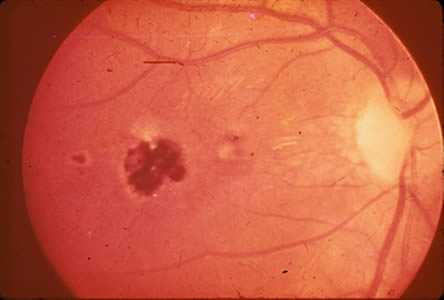

Ocular toxoplasmosis: Chorioretinitis.

Figure A: Severe, active retinochoroiditis.

Figure B: Peripheral retinochoroiditis.

Figure C: Central, healed retinochoroiditis.

Acquired infection with Toxoplasma in immunocompetent persons is generally an asymptomatic infection. However, 10% to 20% of patients with acute infection may develop cervical lymphadenopathy and/or a flu-like illness. The clinical course is usually benign and self-limited; symptoms usually resolve within a few weeks to months. In rare cases ocular infection with visual loss can occur. Immunodeficient patients often have central nervous system (CNS) disease but may have retinochoroiditis, pneumonitis, or other systemic disease. In patients with AIDS, toxoplasmic encephalitis is the most common cause of intracerebral mass lesions and is thought to usually be caused by reactivation of chronic infection. Toxoplasmosis in patients being treated with immunosuppressive drugs may be due to either newly acquired or reactivated latent infection.

Congenital toxoplasmosis results from an acute primary infection acquired by the mother during pregnancy. The incidence and severity of congenital toxoplasmosis vary with the trimester during which infection was acquired. Because treatment of the mother may reduce the incidence of congenital infection and reduce sequelae in the infant, prompt and accurate diagnosis is important. Many infants with subclinical infection at birth will subsequently develop signs or symptoms of congenital toxoplasmosis. Ocular Toxoplasma infection, an important cause of retinochoroiditis in the United States, can be the result of congenital infection, or infection after birth. In congenital infection, patients are often asymptomatic until the second or third decade of life, when lesions develop in the eye.